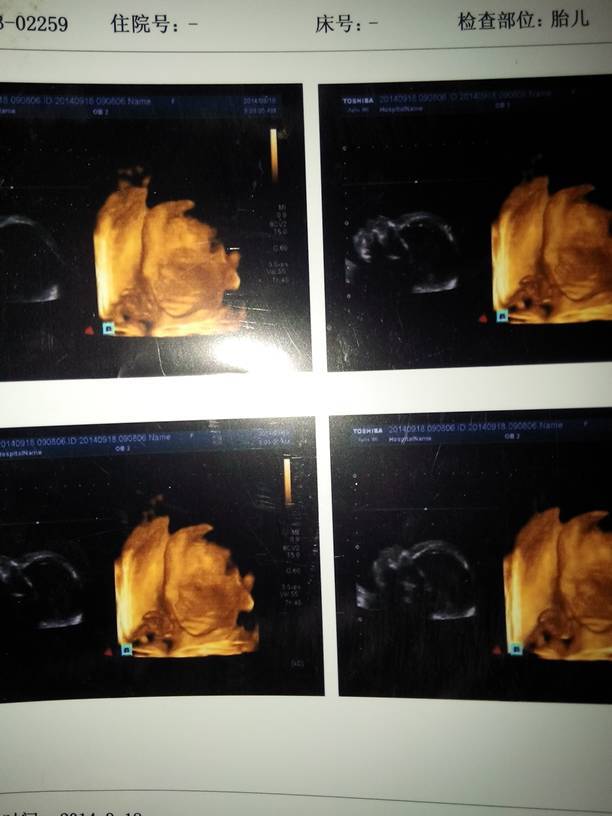

我宝贝的四维这是,有没有宝妈有照片的我想看下可以吗 我宝贝的四维这是,有没有宝妈有照片的我想看下可以吗 点击展开 幸福靠自己_jRuG 2014-11-24 12:53 为您推荐: 其他回答 六个月…… Zhongzhen 2014-11-25 09:59 づ命硬i 2014-11-25 00:06 是的。如果检查的结果比较正常的话,表示胎儿的肢体发育和器官发育非常正常的。平时需要注意休息,加强营养,饮食需要注意全面,清淡,营养的。 shenglongxiao 2014-11-24 14:22 怎么看不到脸呀那些,我24周左右做的都能看出宝宝的五官 晨宝宝妞 2014-11-24 13:54 Zhongzhen 2014-11-24 13:12 加载更多 相关问题 有人有四维图片吗?我想看下谢谢宝妈 我的小宝贝都七个月啦 为什么还坐不稳啊?想问一下宝妈们 宝妈帮忙算一下宝贝多重了